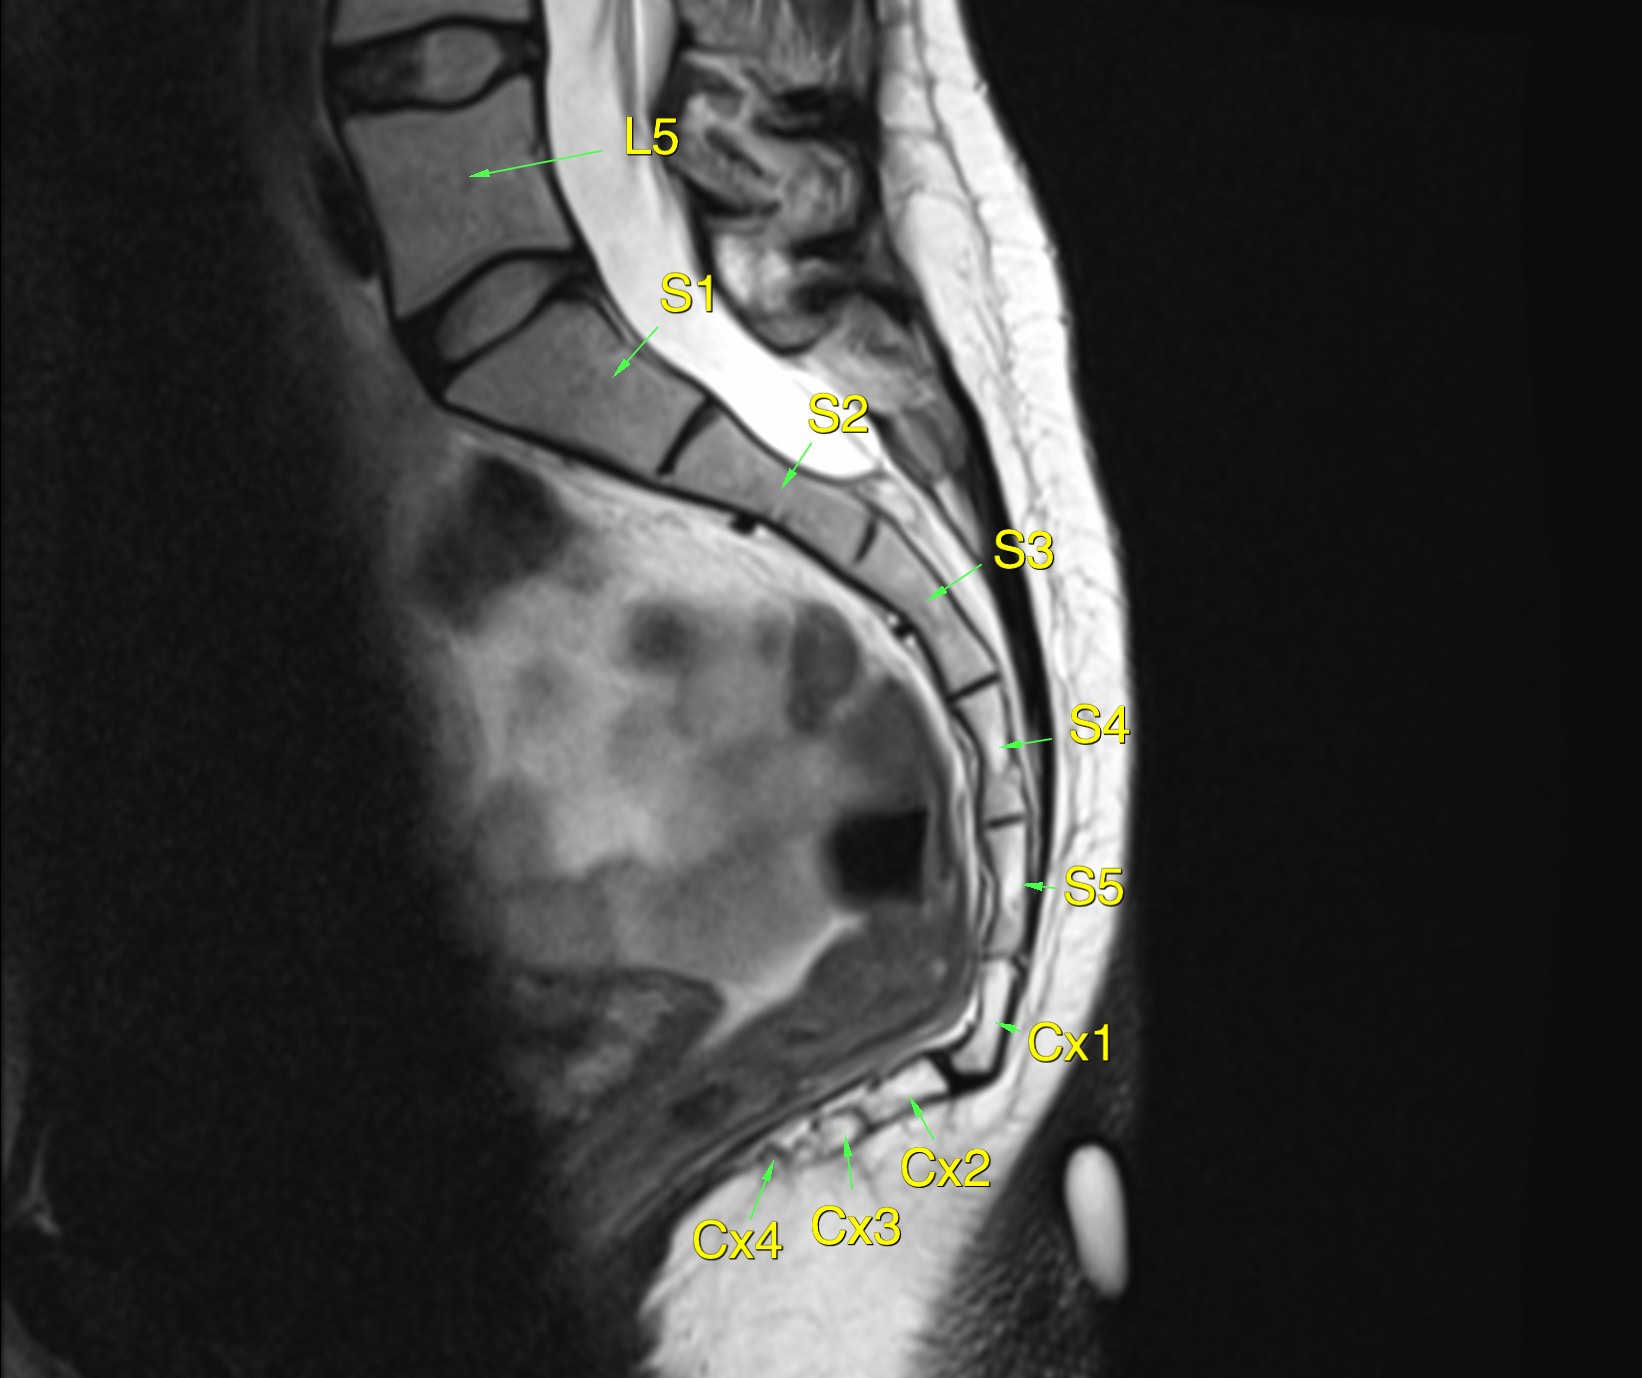

MRI shows the soft tissues of the pelvis, but does not provide as clear a detail of the bones.

Fig 5. MRI coccyx doesn’t show the bones with the high resolution of CT, but shows soft tissues very well. The vertebral bodies are labelled.